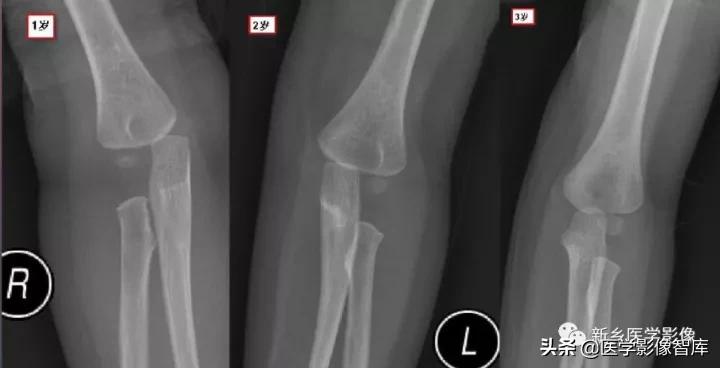

现在简单了,只要记住CRI TOE1-3-5-7-9-11就行了:

- Capitellum (appears age 1-2)肱骨小头1 year - Radial Head (appears age 2-4)桡骨小头 3years- Interanal epicondyle (appears age 4-6)内上髁 5years- Trochlea (appears age 8-11)滑车 7years- Olecranon (9-11 years)鹰嘴 9years- External epicondyle (appears age 10-11)外上髁 11years